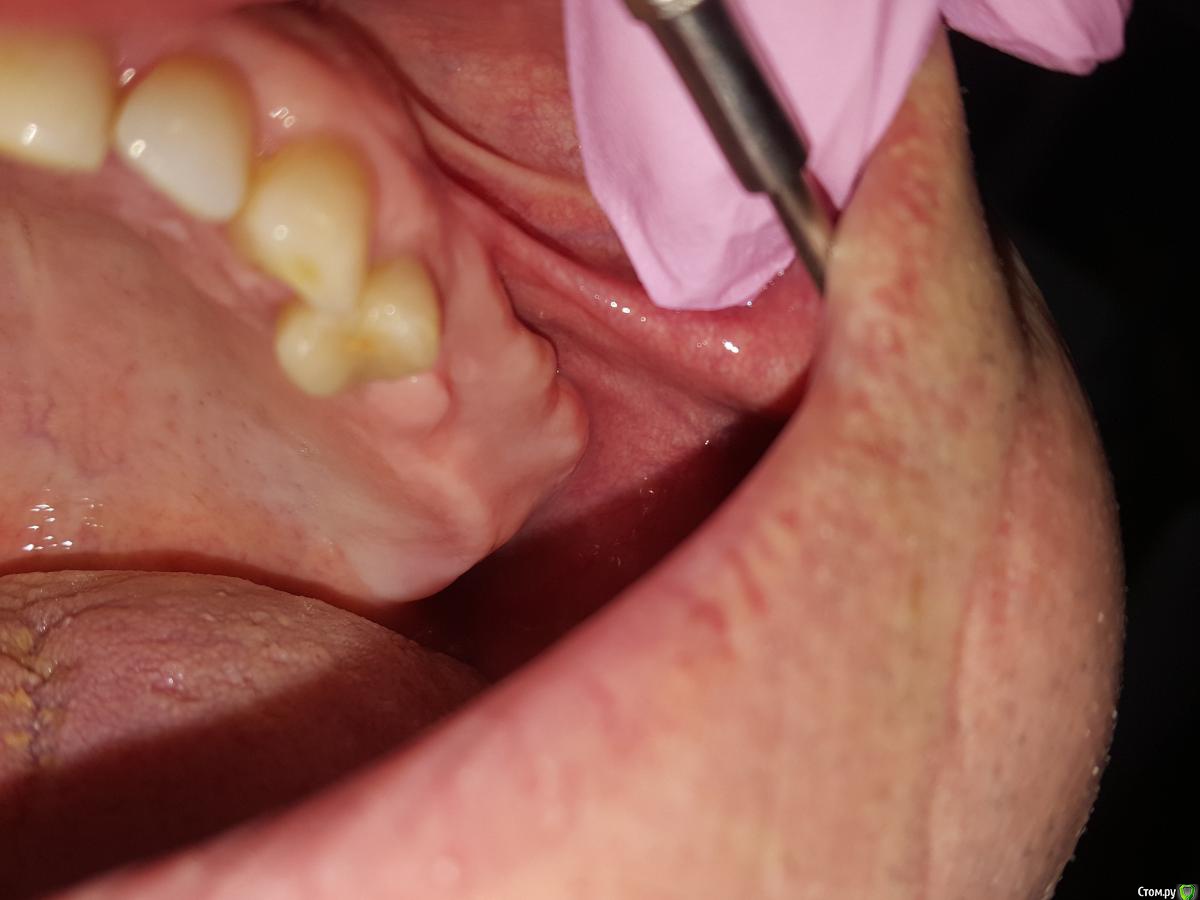

Gennadiy Опубликовано 5 февраля, 2016 Поделиться Опубликовано 5 февраля, 2016 Добрый день, подскажите кто что думает по этому поводу , пациент хочет импланты . Зубы удалены примерно лет назад. Ссылка на комментарий

red_butler Опубликовано 5 февраля, 2016 Поделиться Опубликовано 5 февраля, 2016 Экзостозы, лишней кости радоваться нужно, в пазуху отправите. 15 Ссылка на комментарий